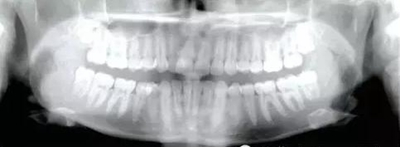

患者為19歲高加索女性,要求矯治中線不齊及上頜右側(cè)側(cè)切牙腭側(cè)異位??趦?nèi)檢查,左側(cè)安氏Ⅰ類(lèi)尖牙、磨牙關(guān)系,右側(cè)安氏Ⅱ類(lèi)尖牙、磨牙關(guān)系;上頜中線右偏4mm,下頜中線右偏2mm,16牙根管治療史,16及47有修復(fù)體;覆蓋5mm,覆合4mm,無(wú)橫向不調(diào)。功能檢查,顳下頜關(guān)節(jié)無(wú)明顯異常,面部及咀嚼肌不對(duì)稱(chēng)。

經(jīng)測(cè)量,上頜第一磨牙遠(yuǎn)中移動(dòng)3.5mm,達(dá)到磨牙Ⅰ類(lèi)關(guān)系,同時(shí)壓低2mm,而第一前磨牙和上頜切牙沒(méi)有明顯的移動(dòng)。上頜第一前磨牙有3°的輕度前傾,這可能是由于上頜只植入了1顆螺紋釘?shù)脑?,作者分析采用兩顆螺紋釘可以減少這種副作用。在上頜磨牙遠(yuǎn)中移動(dòng)過(guò)程中,下頜平面角減少了1°,且其持續(xù)到正畸治療結(jié)束。上頜牙弓寬度有輕度擴(kuò)大。